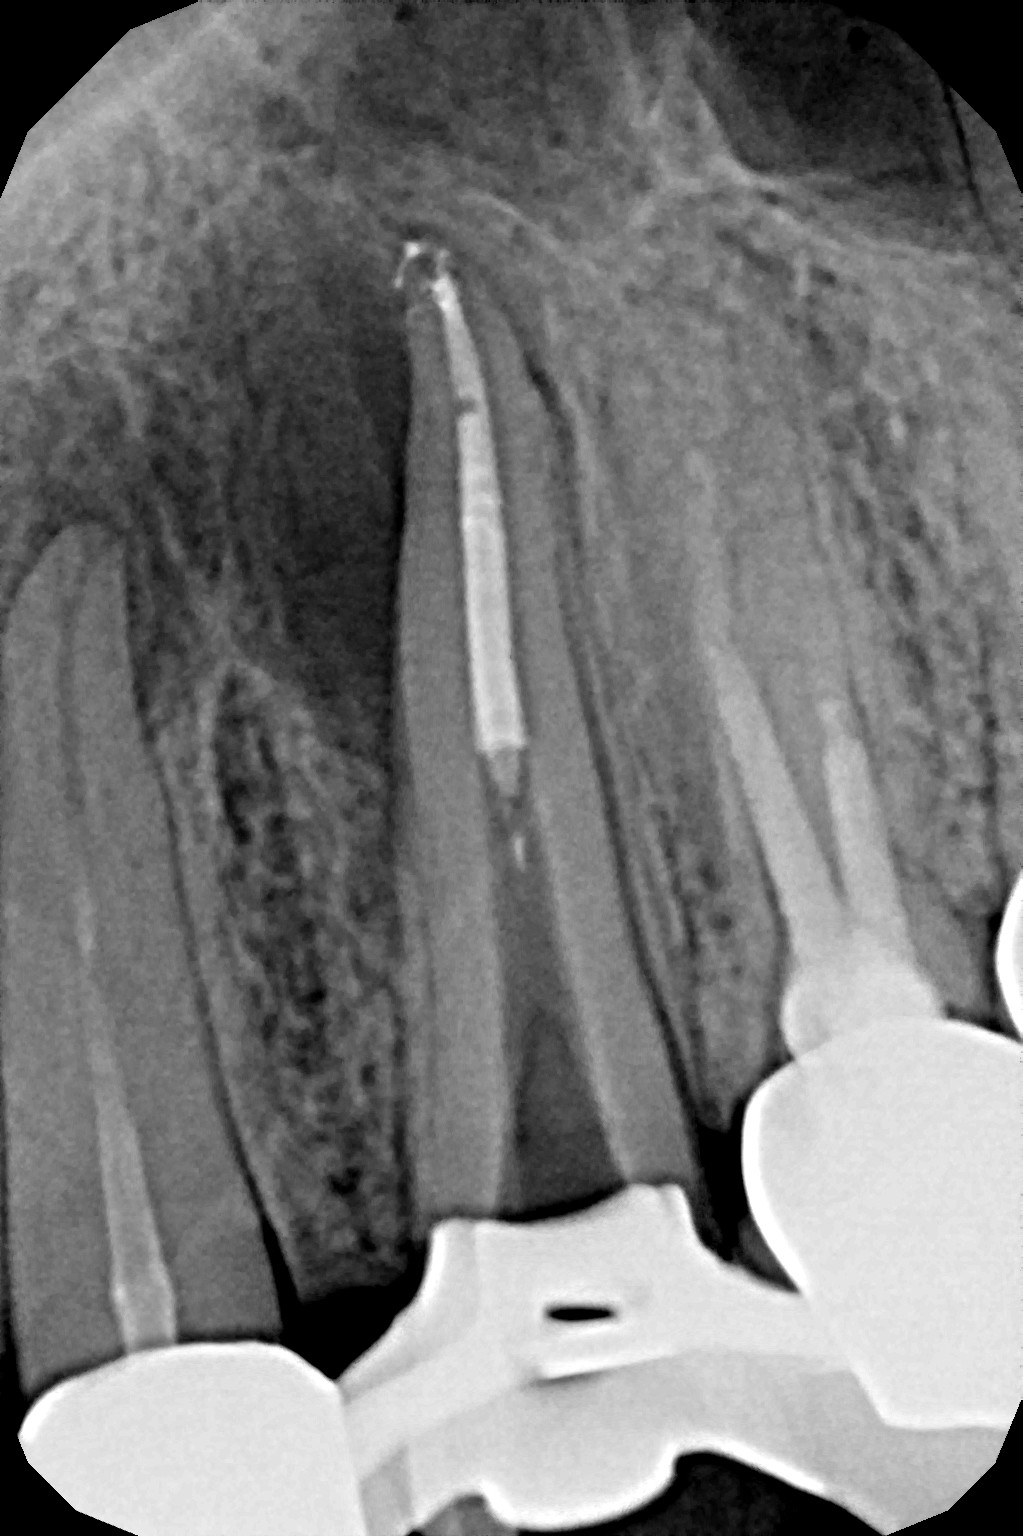

W przypadku zaawansowanych postaci zapaleń miazgi oraz zapalenia tkanek okołowierzchołkowych obraz radiologiczny jest warunkiem rozpoznania. W takiej sytuacji standardem diagnostycznym są zdjęcia przylegające zęba, często wykonywane przy użyciu radiowizjografii na fotelu stomatologicznym w trakcie leczenia zęba. Przydatne jest również badanie RTG OPG pantomograficzne, które pokazuje w dwuwymiarowym obrazie zarówno uzębienie, jak i cały układ kostny szczęki oraz żuchwy.

Podstawowym narzędziem diagnostycznym podczas leczenia jest endometr, elektroniczny miernik długości kanału, którym w trakcie procedury wykonuje się pomiary oraz potwierdza stopień drożności kanału.

Na podstawie zdjęcia rentgenowskiego określa się kształt i długość kanału bądź za pomocą specjalnego urządzenia mierzy się jego długość. Potem lekarz otwiera wejścia do kanału, chroniąc ząb koferdamem, czyli specjalną gumą, zapewniającą sterylność oraz chroniącą przed środkami chemicznymi służącymi do oczyszczania kanału. Używa się do tego zarówno specjalistycznego sprzętu, jak i nowoczesnych mikroskopów, pozwalających na uzyskanie dokładnego obrazu leczonego zęba. Ostatnią czynnością jest wypełnienie materiałem światłoutwardzalnym i zabezpieczenie zęba przed dostaniem się i rozwojem bakterii mogących wywołać wtórny stan zapalny.

By uniknąć niedokładności leczenia, oprócz sumiennego wykonania procedur należy diagnostycznie kontrolować każdy etap leczniczy przy użyciu rtg. Szansą dla niedokładnie wypełnionego kanałowo zęba jest jego powtórne leczenie endodontyczne, zwane REENDO.